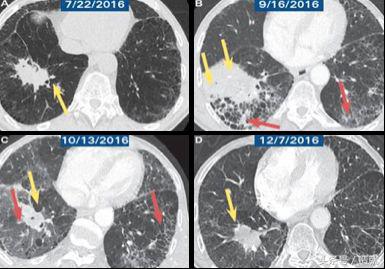

图片右方就是一个用PD-1抗体治疗肺癌的过程,大家可以看到最右下角这个黄色箭头指的地方,肿瘤细胞已经完全消失了,剩下的是少量炎症反应的遗留组织。

一个月之前最新公布的数据显示,使用PD-1抗体,肺癌的存活率可以由原来非常非常低的5%左右,提升到20%以上。必须说,这是一个非常非常令人振奋的进步。